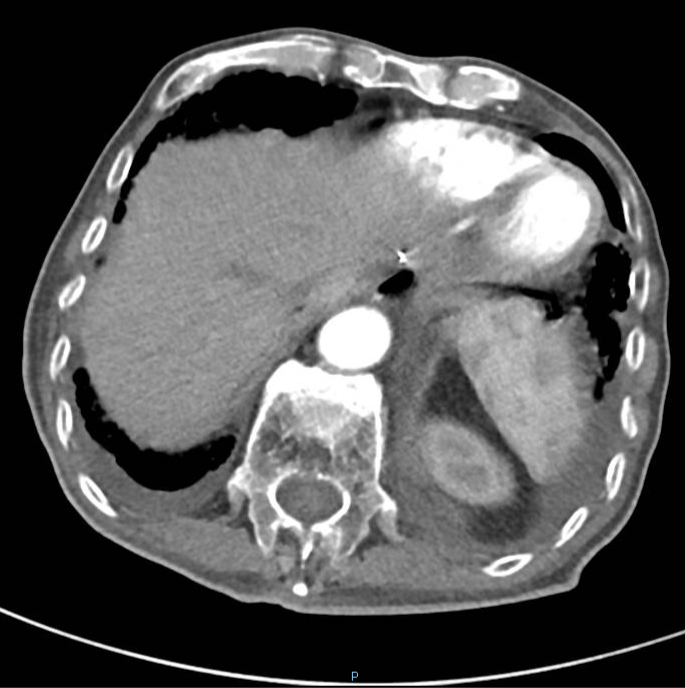

2020-08-31复查腹部CT:与患者前片(2020-1-8)比较显示:所示腹部病变较前未见明显变化。双肺高密度影范围较前缩小。

△ 腹部CT 2020.08